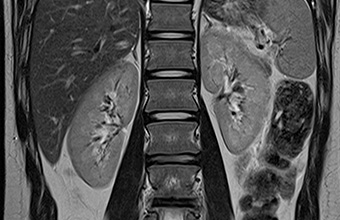

MR unutarnjih organa

MR snimanja unutarnjih organa vrlo su ugodna, tijekom snimanja pacijent može slobodno disati, a najvećem broju slučajeva daje bolje rezultate od endoskopskih tehnika pretraga.

MR u onkologiji

MR u onkologiji poseban je program snimanja bez kojeg je danas nezamislivo rano otkrivanje različitih tumora, raka, nadzor odgovarajućih terapija i kontrola oporavka nakon složenih operacija.